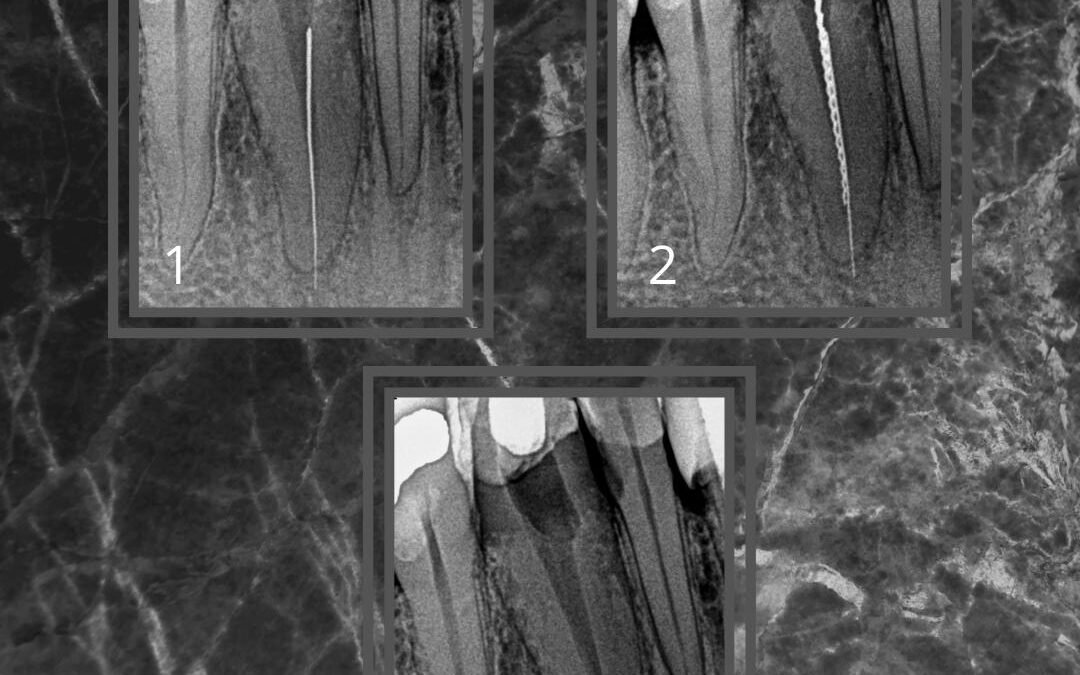

Lima Fraturada que ultrapassou o forame Apical Neste caso, enviado por um colega, havia uma lima fraturada que ultrapassava o forame apical. Devido à grande dificuldade de remoção, por ela estar travada no forame, foi necessário usar uma lima Hedstroem com cola. E...